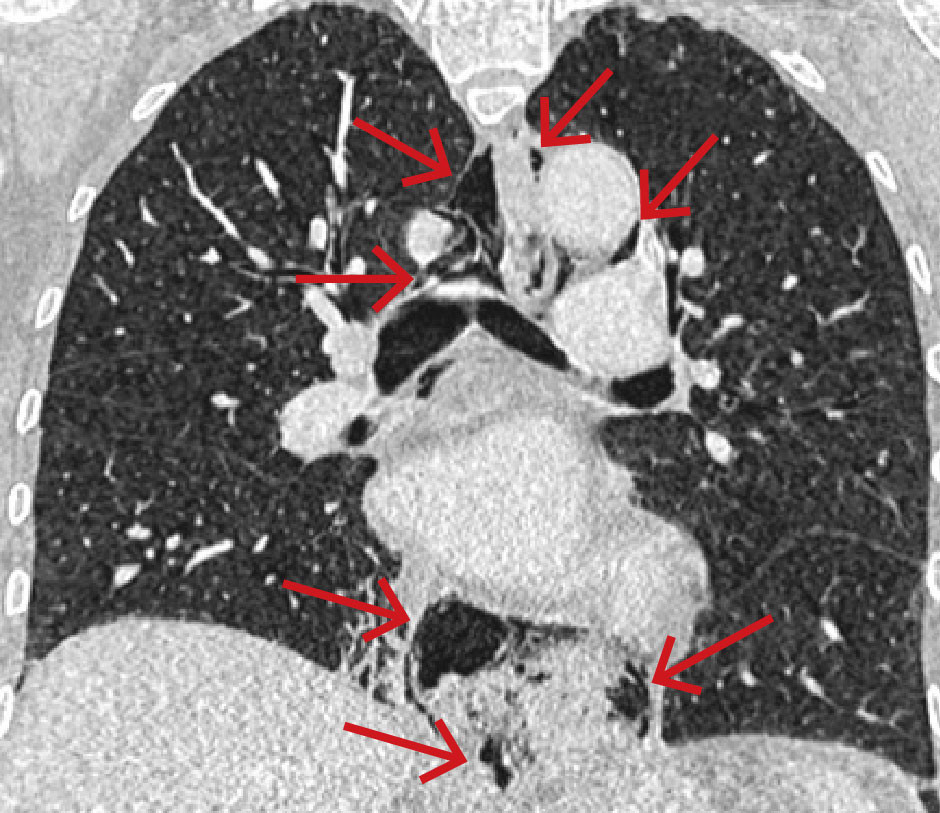

På grunn av uavklarte smerter ble kvinnen undersøkt med CT toraks, abdomen og bekken med intravenøs kontrast. Undersøkelsen viste spredte små luftlokulamenter i bløtdeler på hals, i mediastinum, langs øsofagus og i øvre abdomen i tilslutning til cardia ventriculi (figur 1). Hun hadde også beskjedne mengder pleuravæske bilateralt og beskjedne fortetninger deklivt i høyre underlapp.

Det påfølgende døgnet etter prosedyren fikk pasienten feber, økende tungpustethet og redusert allmenntilstand. Dette ble oppfattet som tegn på lekkasje av øsofagusinnhold til mediastinum og øvre abdomen. For å avklare forverringen med henblikk på utvikling av mediastinitt, ble det gjort ny akutt CT-undersøkelse med intravenøs kontrast. Denne viste økning av subkutant emfysem, pleuravæske, pneumomediastinum og luft i fettvevet i øvre abdomen. I tillegg var det tilkommet et 4,5 cm lokulament med luft og lavattenuerende innhold samt kontrastladende avgrensning forenlig med abscess i høyre mediastinum paraøsofagealt med tilgrensning til diafragma, pleura og perikard.